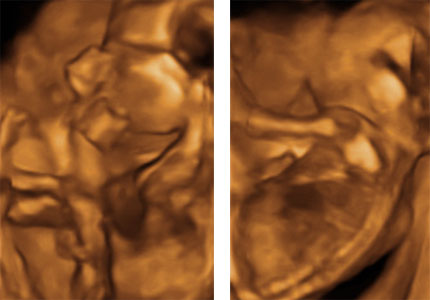

[quote="dorkamartini"]a írta:dorkamartini második kettős képen miután kortyolgatott éppen mosolyog és mivel direkt ettem fincsi édeset előtte így látni a mellette levő képen ahogy kidugja a nyelvét mert aaaaannnnyira fincsi:))))))